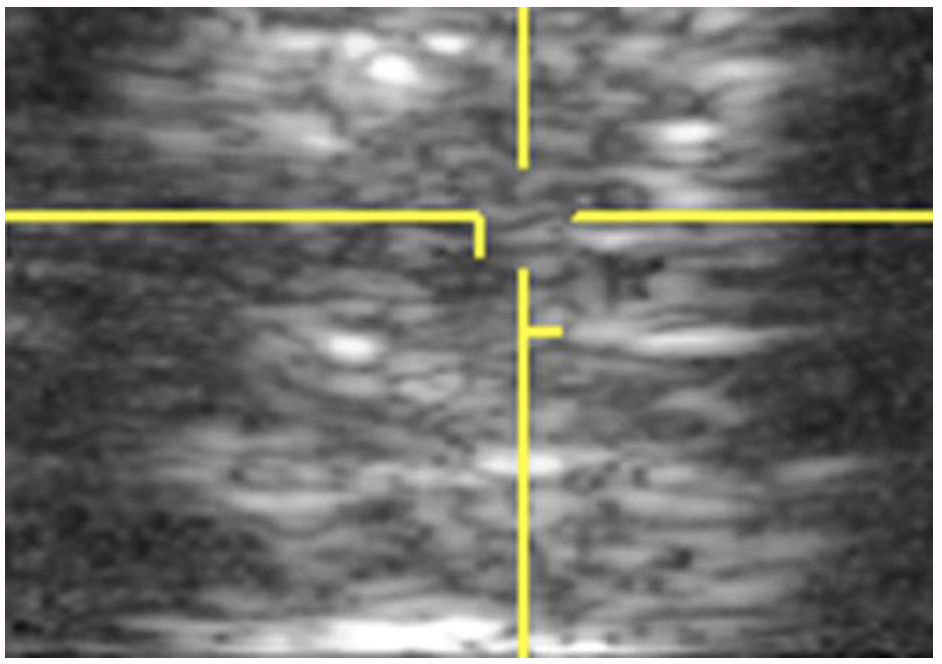

Courtesy, Hans T.M. van Schie, DVM, PhD

Recently, in both human and veterinary medicine, the technique of ultrasound tissue characterization, also known as UTC, has been utilized to fill in the gaps created by traditional ultrasound. In this technique, a standard ultrasound probe is placed in a motorized tracking device. This device is placed on the horse’s skin over the tendons. The probe is automatically moved along a track that allows it to uniformly scan a length of leg. A 12-centimeter length is scanned in 45 seconds. Images are captured every 0.2 millimeters. The over 600 images and information produced are digitally manipulated to generate a 3D tendon representation.

This precise “spatial stacking” of images provides a much more detailed and accurate representation of the tendon and various areas along the scanned length. This is proving extremely helpful, as most tendon injuries are found to involve varying lengths and depths along the limb with pockets of better fibers intermixed with areas of more serious damage. This subtlety is missed with a standard ultrasound but is better defined with 3D tissue characterization.